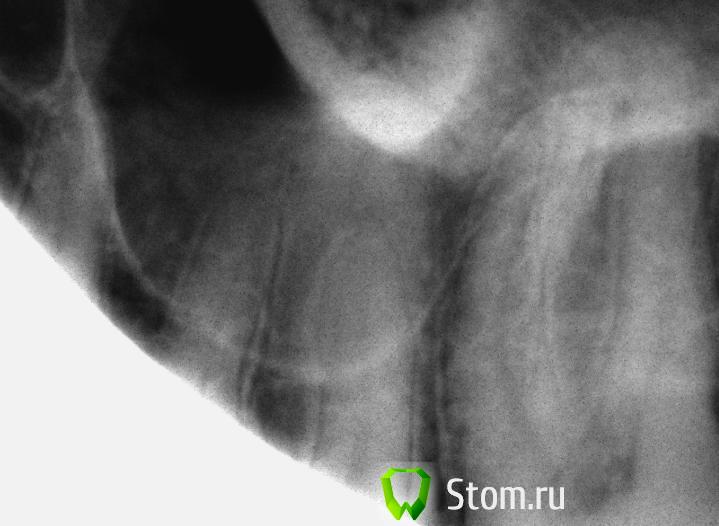

айка Опубликовано 27 февраля, 2012 Поделиться Опубликовано 27 февраля, 2012 Мне кажется там гайморит. На третьем снимке горизонтальный уровень просматривается. Ссылка на комментарий